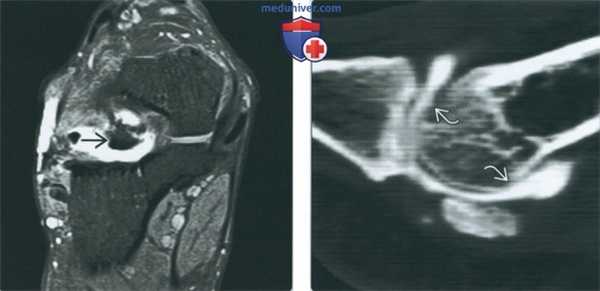

(Слева) МР-артрография в режиме Т1ВИ FS, аксиальный срез: визуализируется разрыв латеральной коллатеральной связки вследствие травматического приведения большого пальца. Отмечаются проксимальная ретракция волокон ЛКС и распространение контрастного препарата через дистально расположенный дефект. МКС не изменена.

(Справа) МР-артрография в режиме Т1ВИ FS, коронарный срез, этот же пациент: определяется дефект ЛКС. Мягкие ткани подошвы не изменены. (Слева) МР-артрография в режиме Т1ВИ FS, коронарный срез: определяется распространение контрастного препарата через дефект в проксимальном крае подошвенной связки 1-го плюснефалангового сустава вследствие избыточного тыльного сгибания большого пальца.